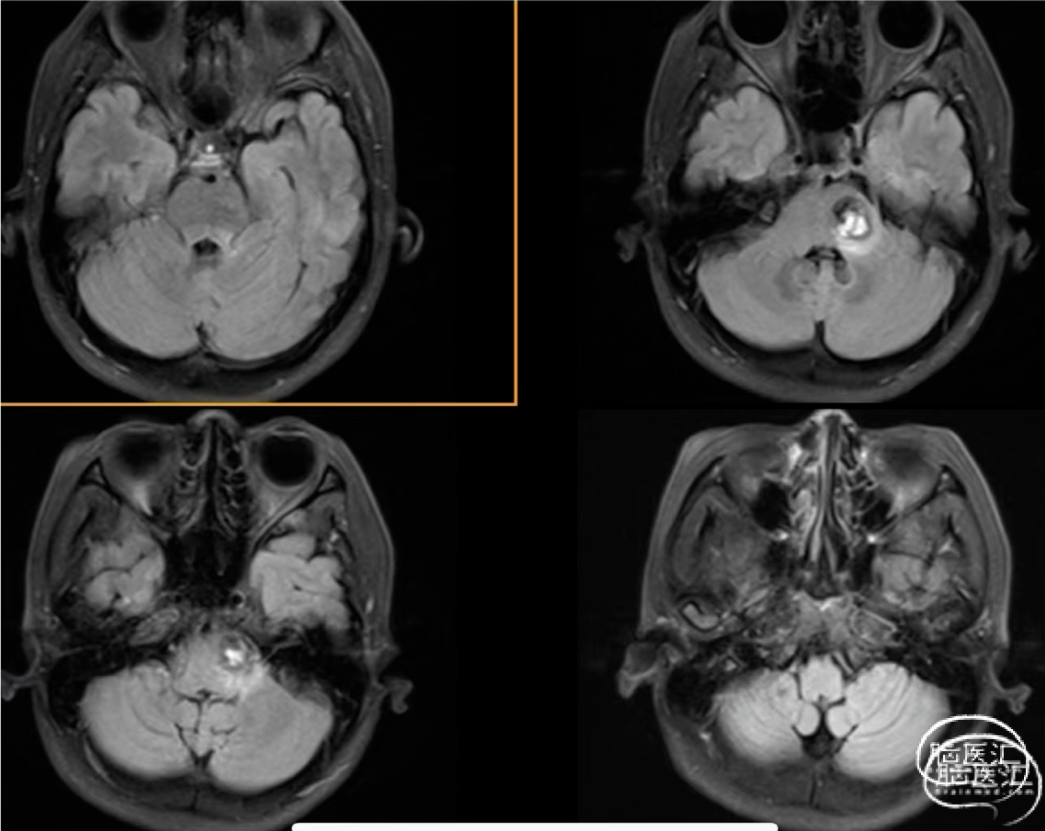

病例二

女,39岁,头痛伴四肢麻木半个月,BSCMs评分0。

图12

plan A

plan B